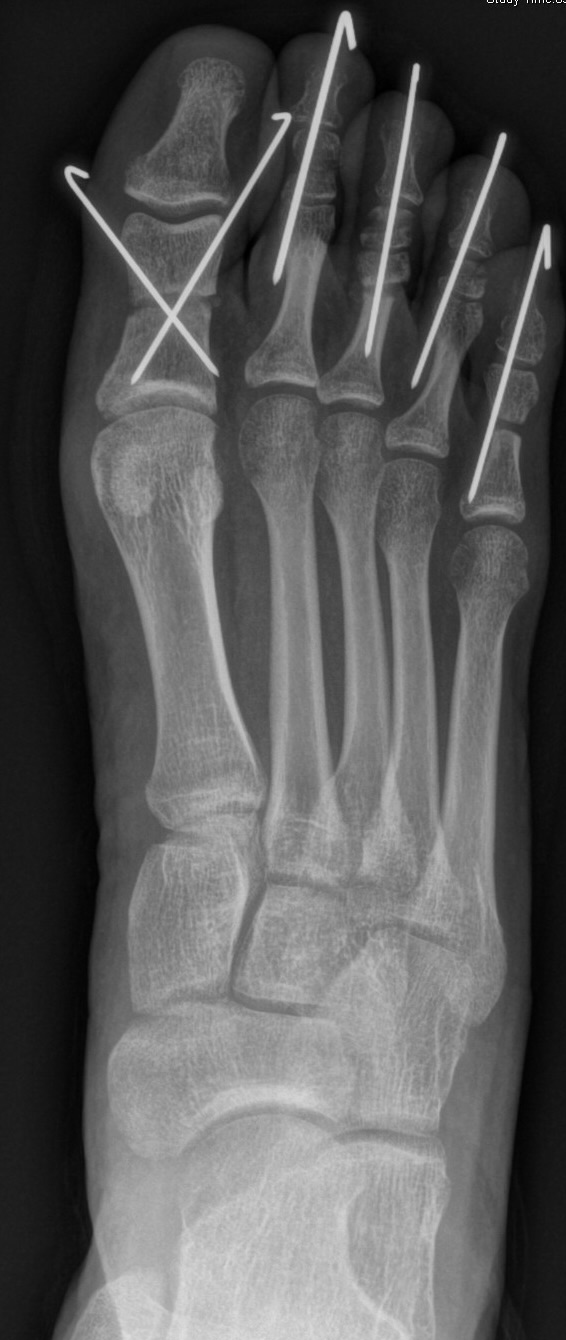

Die Chevron Osteotomie 1 ist ohne Komplikationen am wachsenden Skelett durchführbar. Das Metatarsale I besitzt distal keine Wachstumsfuge, die geschädigt werden könnte. Die „französische Methode nach Marc Elkaim“ eignet sich für Kinder ganz besonders (Abb. 28).

Abb. 28 a-g: Radiologischer Verlauf einer Chevronosteotomie nach dem Verfahren von M. Elkaim mit prä- (a-c drei unterschiedliche Ansichten) und intraoperativen Röntgenbildern in zwei Ansichten (d-e) sowie postoperativ zwei Ansichten (f-g).

Sie wird über eine eigene Tapetechnik fixiert und kann bei einem erhöhten Intermetatarsale-Winkel alternativ zur Scarf-Osteotomie durchgeführt werden. Nachteile der Methode sind eine deutliche Verkürzung durch die Fräse sowie eine starke Plantarisierung des Metatarsale I Köpfchens. Um die Verkürzung zu vermeiden, wird verlängernd in Richtung des Metatarsale II Köpfchens (nicht wie offen in Richtung Metatarsale IV Köpfchen) osteotomiert. Gleiches gilt für die starke Plantarisierung, die durch den Knochenverlust der Fräse entsteht. Die Korrektur eines kindlichen oder jugendlichen Hallux valgus ist mit der Methode ansonsten suffizient durchführbar. Wird verkürzt, muss ausreichend plantarisiert werden, um eine Transfer-Destabilisierung MT II-IV zu vermeiden.